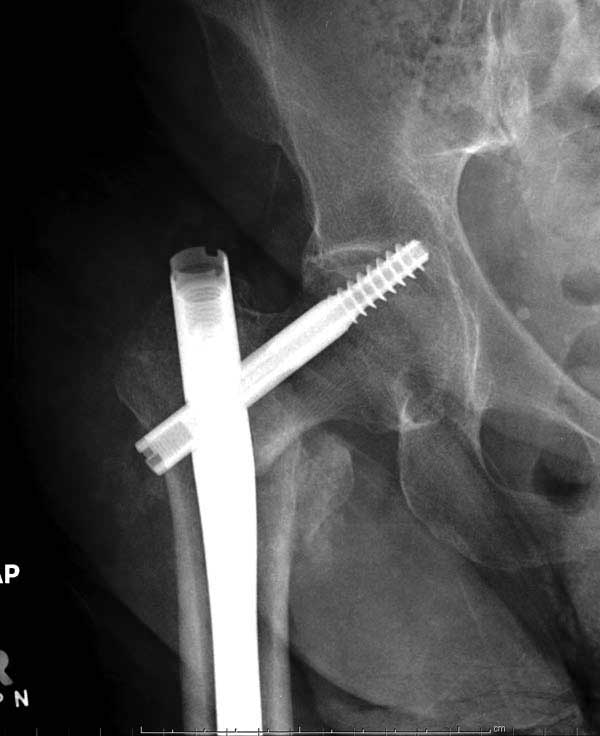

Прилагаю снимок сделанный еще в стационаре через 2 недели после операции.

Проблема основная тут в остаточном варусе. Даже если отломки по медиальной стенке при этом окажутся в контакте, от cutout это не спасет. Плюс короткий винт, еще и эксцентрично расположенный, так что совсем мало кости ему резать надо.

Первые снимки показывают технические погрешности установки DHS. Не была достигнута репозиция, конечность в флексии и шейка в ротации. Сегодня все меньше обращают внимание на параметры для оценки репозиции (S контуры Lowell в обеих проекциях и Garden Alignment Index, в норме 155 и 180 градусов), хотя такие простые тесты помогли бы дорепонировать смещение. Винт находится сзади в головке, что при нагрузке поменяет вектор и вместо компрессии в линии перелома срежет головку-Cut Out!

В зависимости от дистанции линии перелома и латерального кортекса надо использовать разной длины barrel, т.е. конец баррели не должен доходить до пределов перелома. Здесь конец длинного ствола упирается в медиальный фрагмент, что мешает созданию компрессии, а более короткий barrel создал бы запас для компрессии. В боковой пластине вместо 4х можно было ограничится двумя шурупами, потому что головка шурупа в 4.5 мм выдерживает давление до 350 кг.

Вторая операция- это фаза сохранения головки бедра. Желательно приложить все усилия и сохранить головку, но, как видно, “фиаско” продолжается. Здесь вместо нейтрализации сил между медиальной и латеральными сторонами была попытка удержать варус. Варус не удержать ни деротационными шурупами о котором говорили и не костными стружками вбитые в шейку, потому что вся нагрузка упирается в головку.